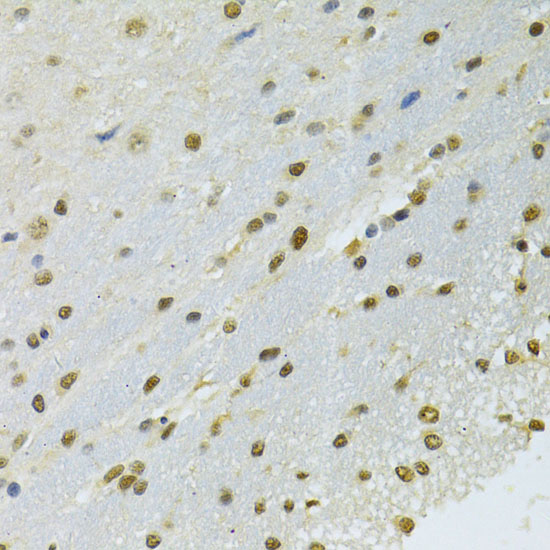

Immunohistochemistry of paraffin-embedded rat brain using NLK antibody at dilution of 1:100 (40x lens).